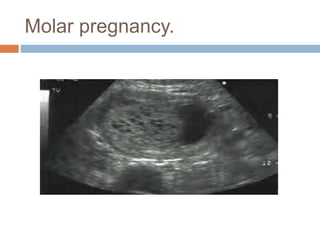

Molar pregnancy.